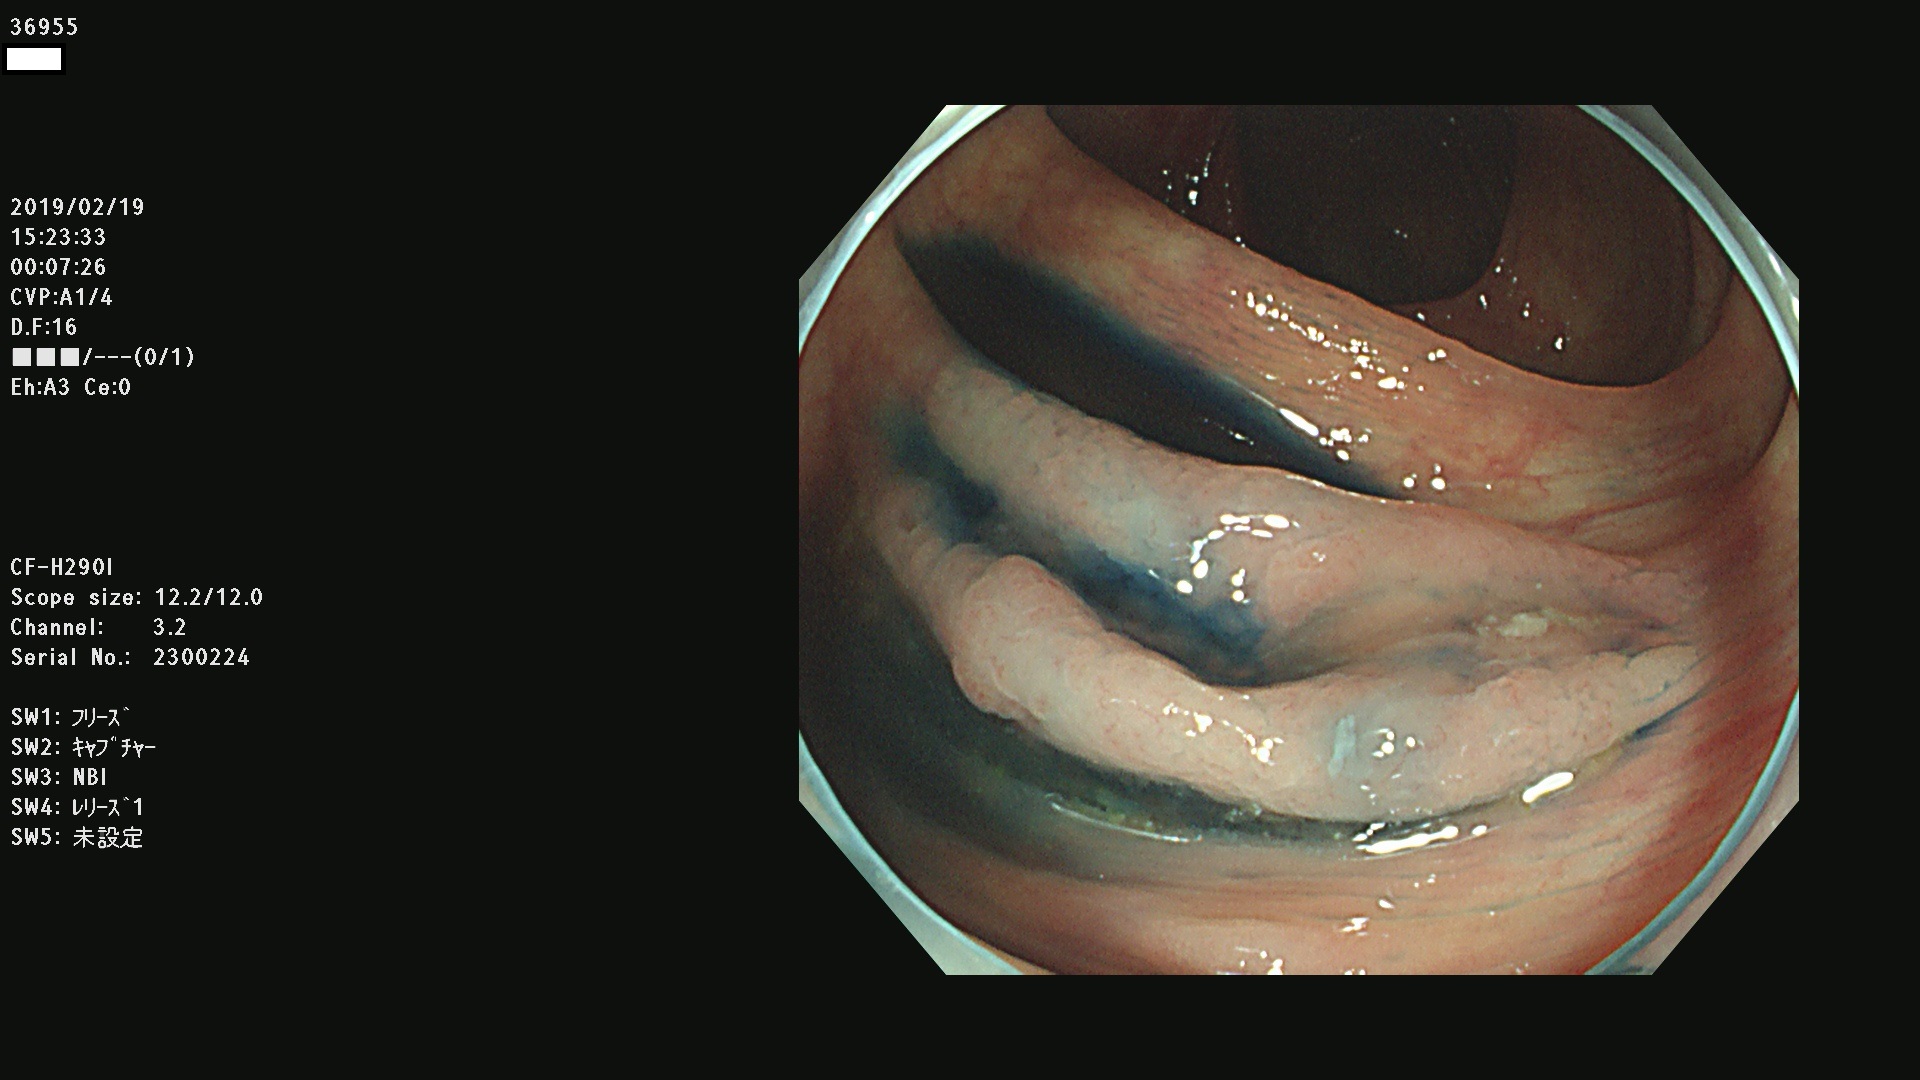

腺腫発見率 67 % (カルテ番号 36900〜36999の100名の方の検査結果で集計)大腸癌検診最新情報

以下のカルテ番号の方に腺腫(Adenoma,Group3〜5)が見つかりました(集計法)

36900 36901 36903 36904 36905 36908 36909 36910 36911 36913 36914 36915 36916 36917 36918 36919 36920 36923 36924 36925 36927 36928 36930 36931(SSAPのみ) 36933 36935 36936 36937 36941 36943 36944 36945 36946 36949 36951 36953 36954 36955 36957 36963 36965 36966 36967 36968 36969 36970 36974 36975 36976 36977 36978 36979 36980 36981 36983 36984 36986 36987 36988 36989 36990 36991 36993 36994 36996 36998 36999

発見困難で危険性の高い平坦型病変(上記100名より抽出) ![]()